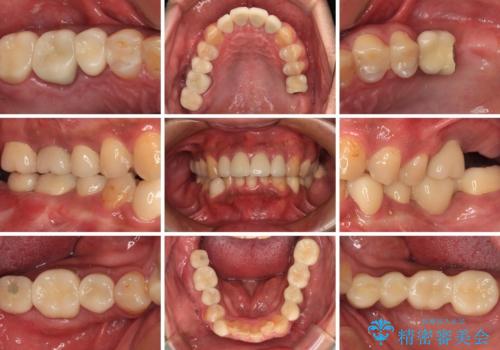

- 黄ばんだ前歯や目立つ奥歯の銀歯をきれいにしたいとのことで来院された患者様です。

欠損している歯や、割れてしまって抜歯の必要な歯などがあり、咬合力が強いため欠損部はインプラント補綴を前提に治療を行うこととしました。

しかしながら、左下の抜歯部位は骨欠損が著しく大きく、多大な垂直的骨造成を要するため、3歯を支台としたブリッジによる補綴治療とし、右下のみをインプラント補綴としました。

小さい修復物の銀歯が装着されている歯はセラミックインレーにて、その他はオールセラミッククラウンにて補綴治療を進めることとしました。

矯正治療にも最初は興味を持たれていましたが、抜歯矯正の可能性が高いことや、治療期間、後戻り防止のためのマウスピース使用などが煩わしいと感じ、補綴治療のみを行うこととなりました。